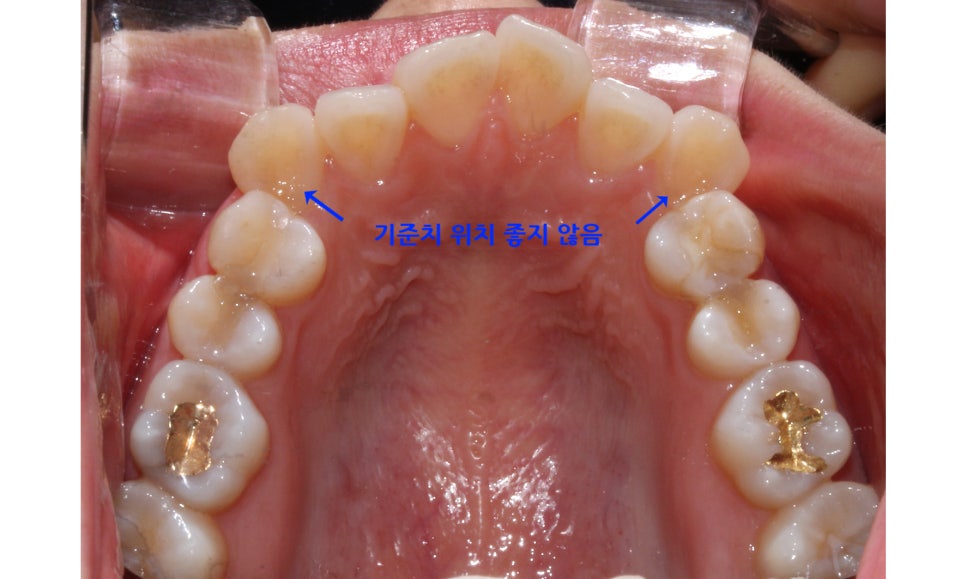

송곳니덧니 case의 상악 교합면 사진을 보시면

송곳니의 위치가 심하게 어긋나 있는 모습을 볼 수 있습니다.

부분교정의 경우 교정장치 부착의 기준이 되는

송곳니(견치)의 위치가 큰 영향을 받기 때문에

위의 Case처럼 기준치의 위치가 틀어진 경우

부분교정보다는 전체교정을 추천드립니다.